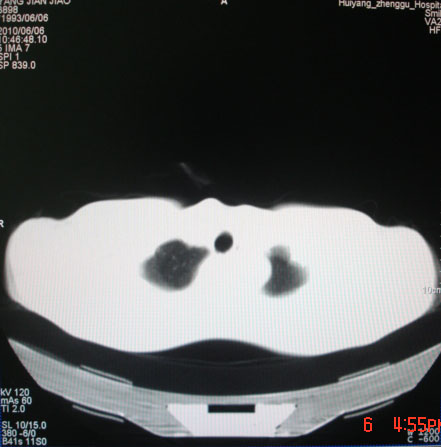

标题: CT26938:单发肺窗

病人17岁。咳嗽伴血丝痰2年?外院x片示左上肺椭圆形影,疑胸腺瘤

建议上传纵隔窗

左肺尖见占位,建议上传纵隔窗及向上扫描。

左上纵隔占位性病变?

(请补传纵隔窗)